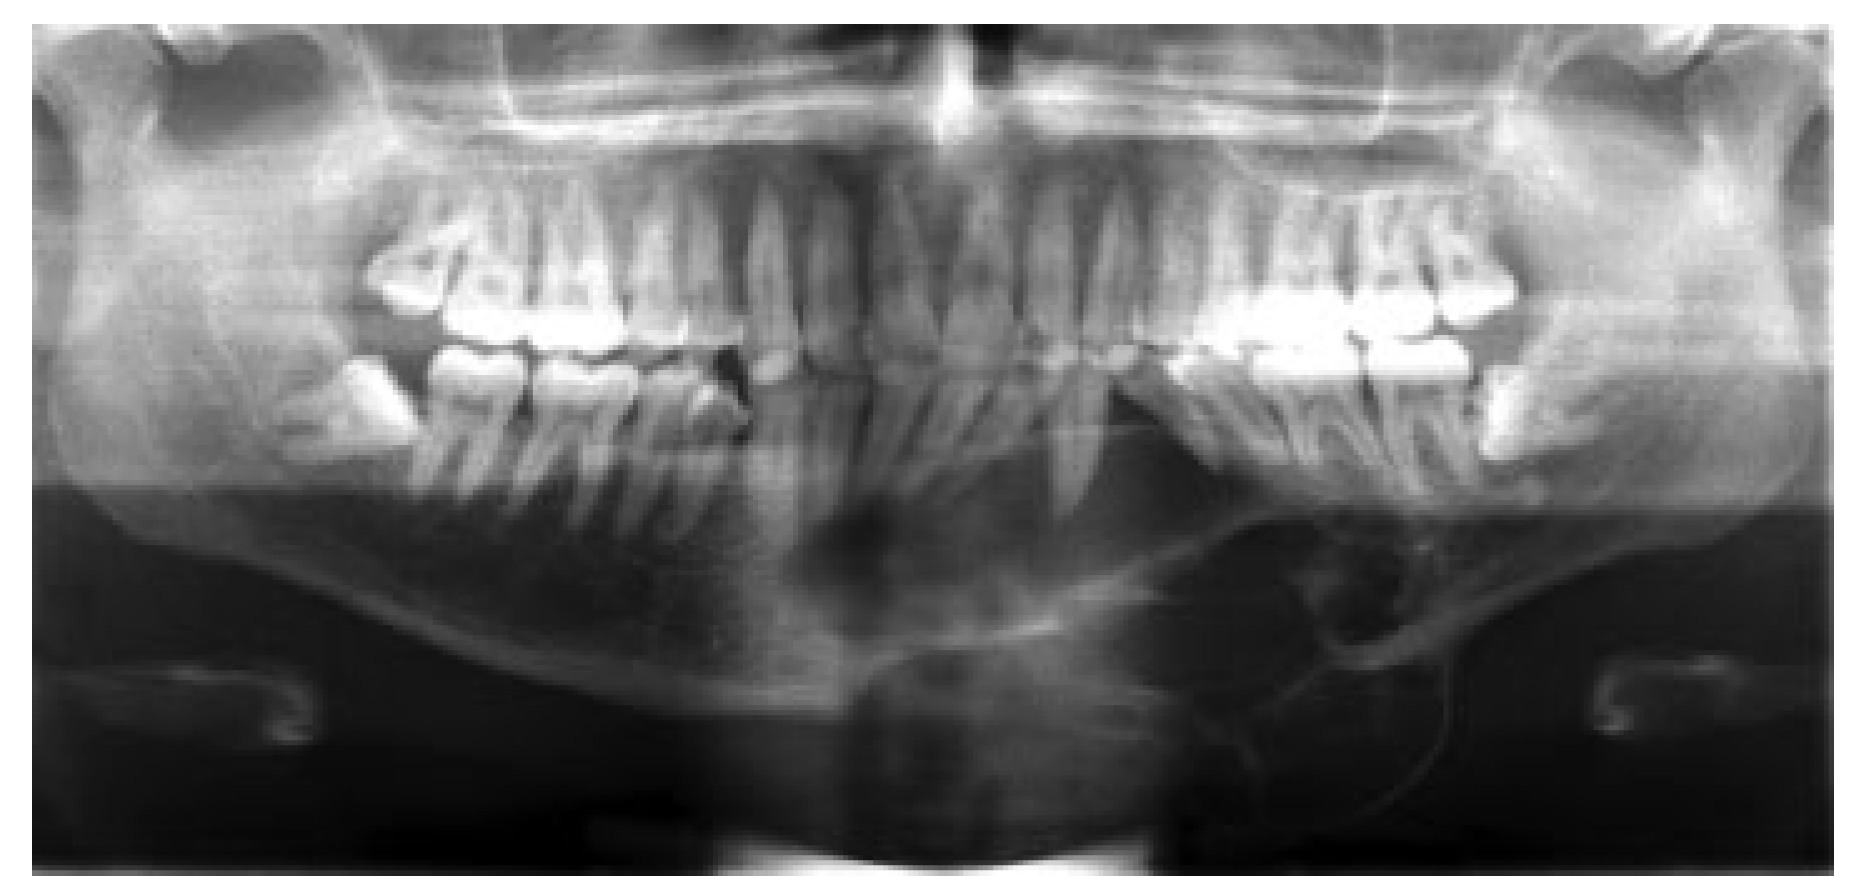

The fourth case was a 9-year-old white male referred to our service with a biopsy-proven ameloblastoma of the right mandible. Panoramic radiographic examination showed a unilocular radiolucent lesion extending from the right first mandibular molar up into the ascending ramus (Figure 4). A high-resolution CT scan was followed by the construction of a three-dimensional model (Figure 5). The resection with 1-cm margins was planned over the model extending vertically from the right sigmoid notch to the gonial angle and anteriorly through to the ipsilateral first premolar. Because of the marked lateral expansile nature of the lesion, the model and the specimen (prior to resection) were altered at the area of the inferior border to facilitate hardware adaptation (Figure 6). A prebent reconstruction plate was obtained and sterilized preoperatively. The resection was performed via a combined transoral and transcutaneous approach. Screw holes were drilled using the prebent plate as a template prior to completing the osteotomies. This was done to ensure correct position of the segments. After the resection, the plate was repositioned without modification utilizing the previous predrilled holes (Figure 7). The occlusion was assessed intraoperatively and was found to be unchanged from preoperatively. The total surgical time was 3 hours and 34 minutes.

Figure 4. Preoperative panoramic radiograph showing unilocular radiolucent lesion at the left mandible. Significant tooth displacement is noted. Case 4.